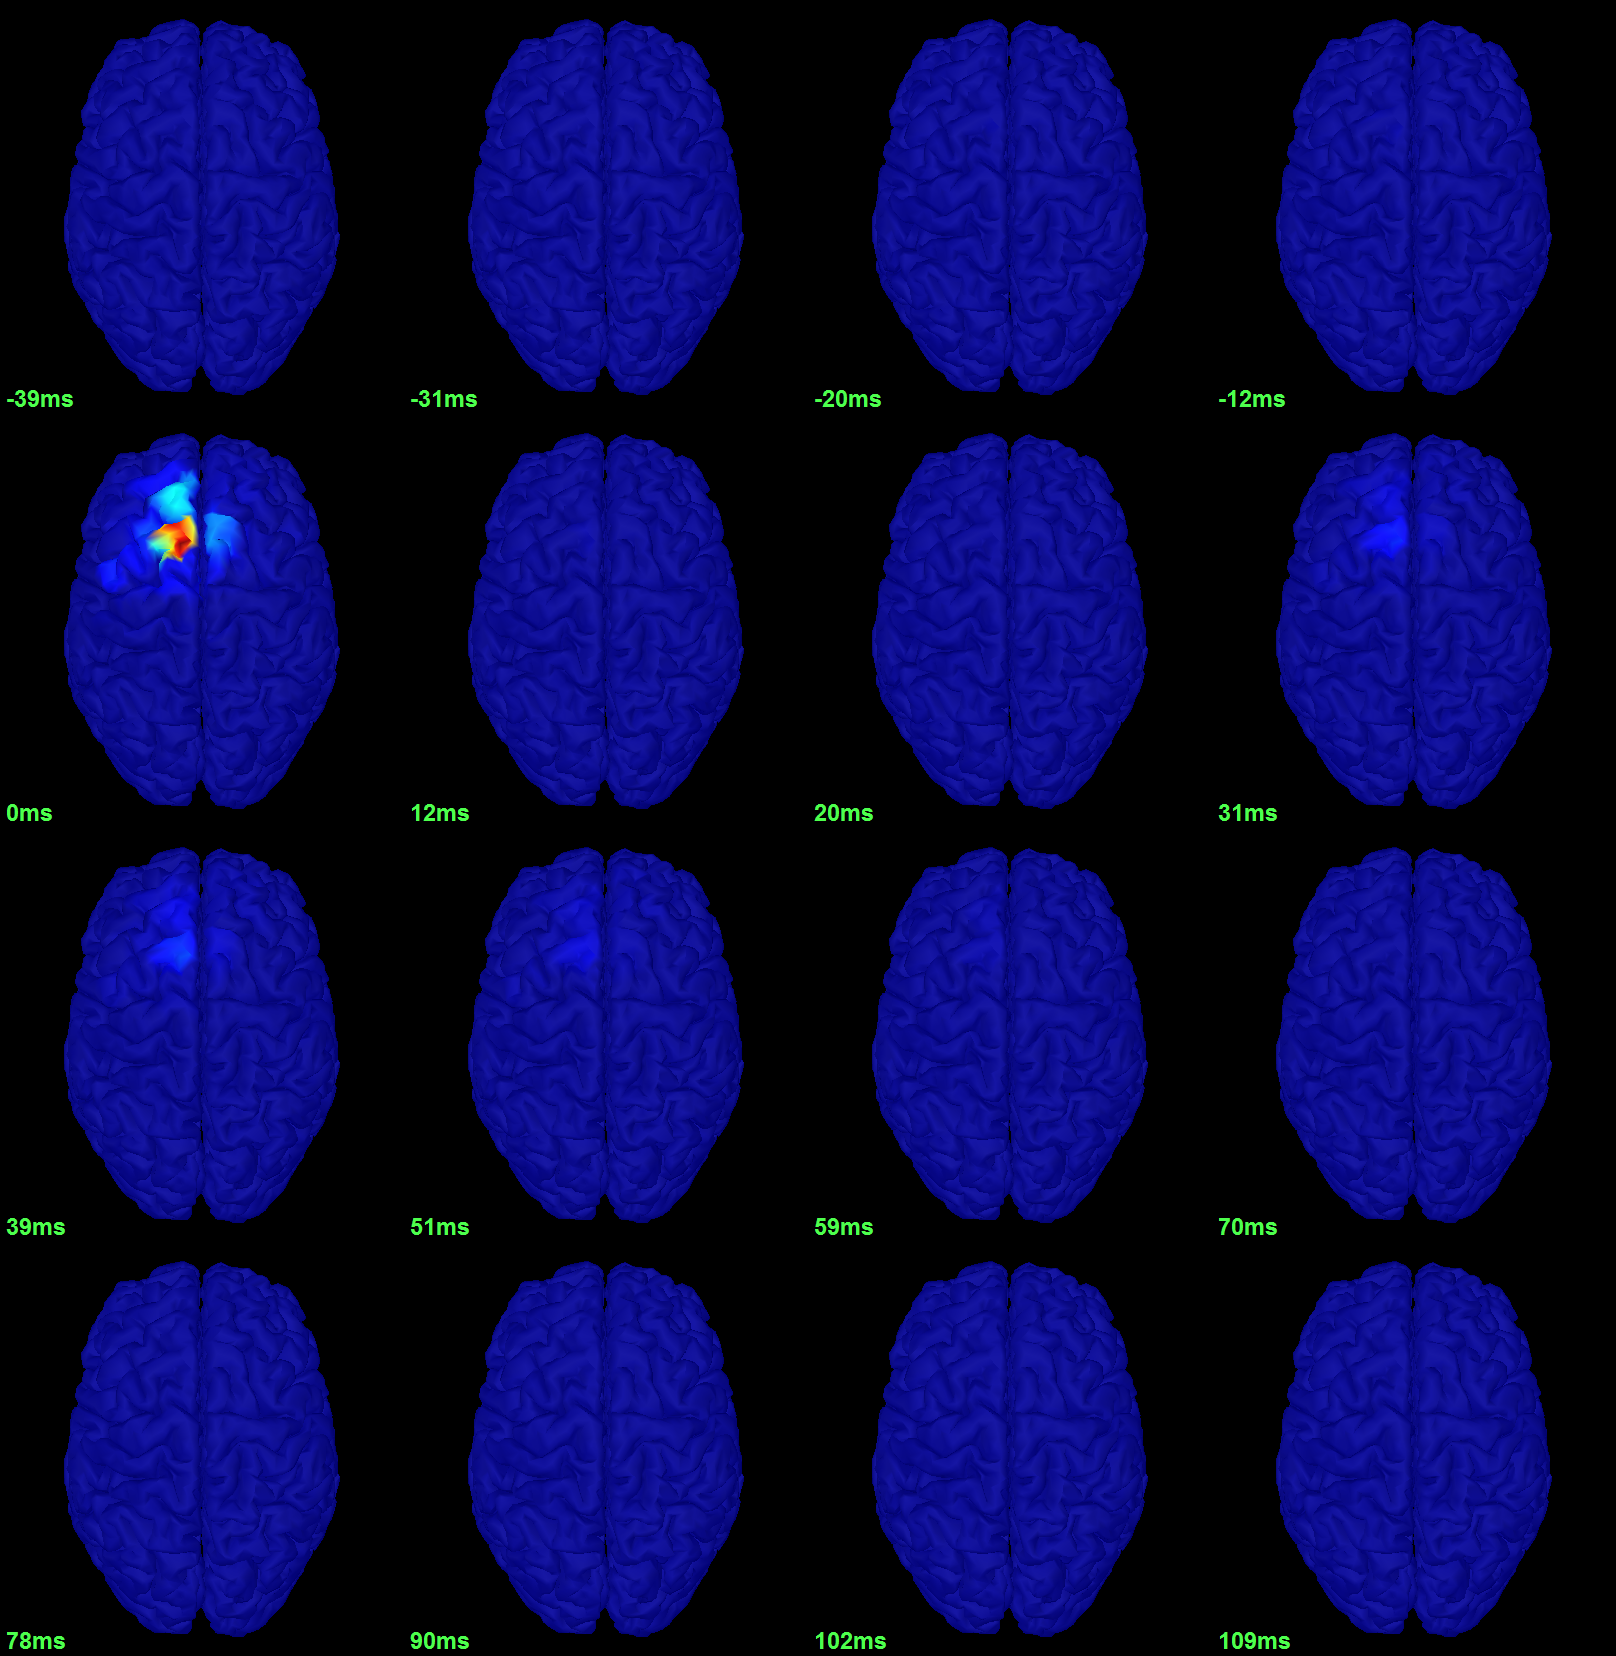

To get a synthetic view at the sensor level of the evolution of the 2D map in time:

Right-click on the figure > Snapshot > Time contact sheet: Figure: [-40ms, 110ms], 16 images.